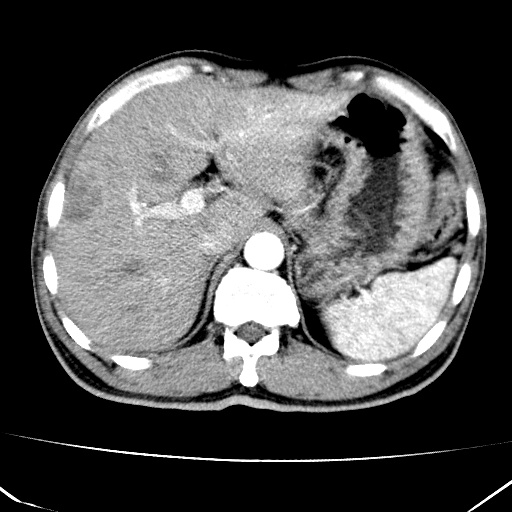

标题: CT17975:请求会诊。男、57岁。上腹部胀痛2天。临床诊断:糜 [打印本页]

标题: CT17975:请求会诊。男、57岁。上腹部胀痛2天。临床诊断:糜

考虑---胃癌肝脏转移可能---建议---胃镜

肝脏多发类圆形低密度影,考虑肝脏转移瘤,肝胃韧带一淋巴结肿大,原发?胃癌?

考虑胃癌肝脏转移可能性大。

考虑胃癌并肝脏及腹膜后淋巴结转移;不排除淋巴瘤。

肝内转移瘤,腹腔及腹膜后淋巴结转移。

考虑胃癌肝脏转移可能性大。应要求上腹部检查时常规准备。